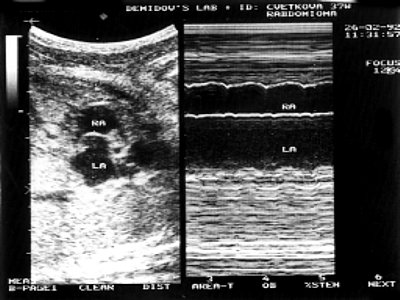

Рис. 2. В и М-сканирование на уровне межпредсердной перегородки, демонстрирующее отсутствие сообщения между предсердиями.

LA - левое предсердие, RA - правое предсердие.